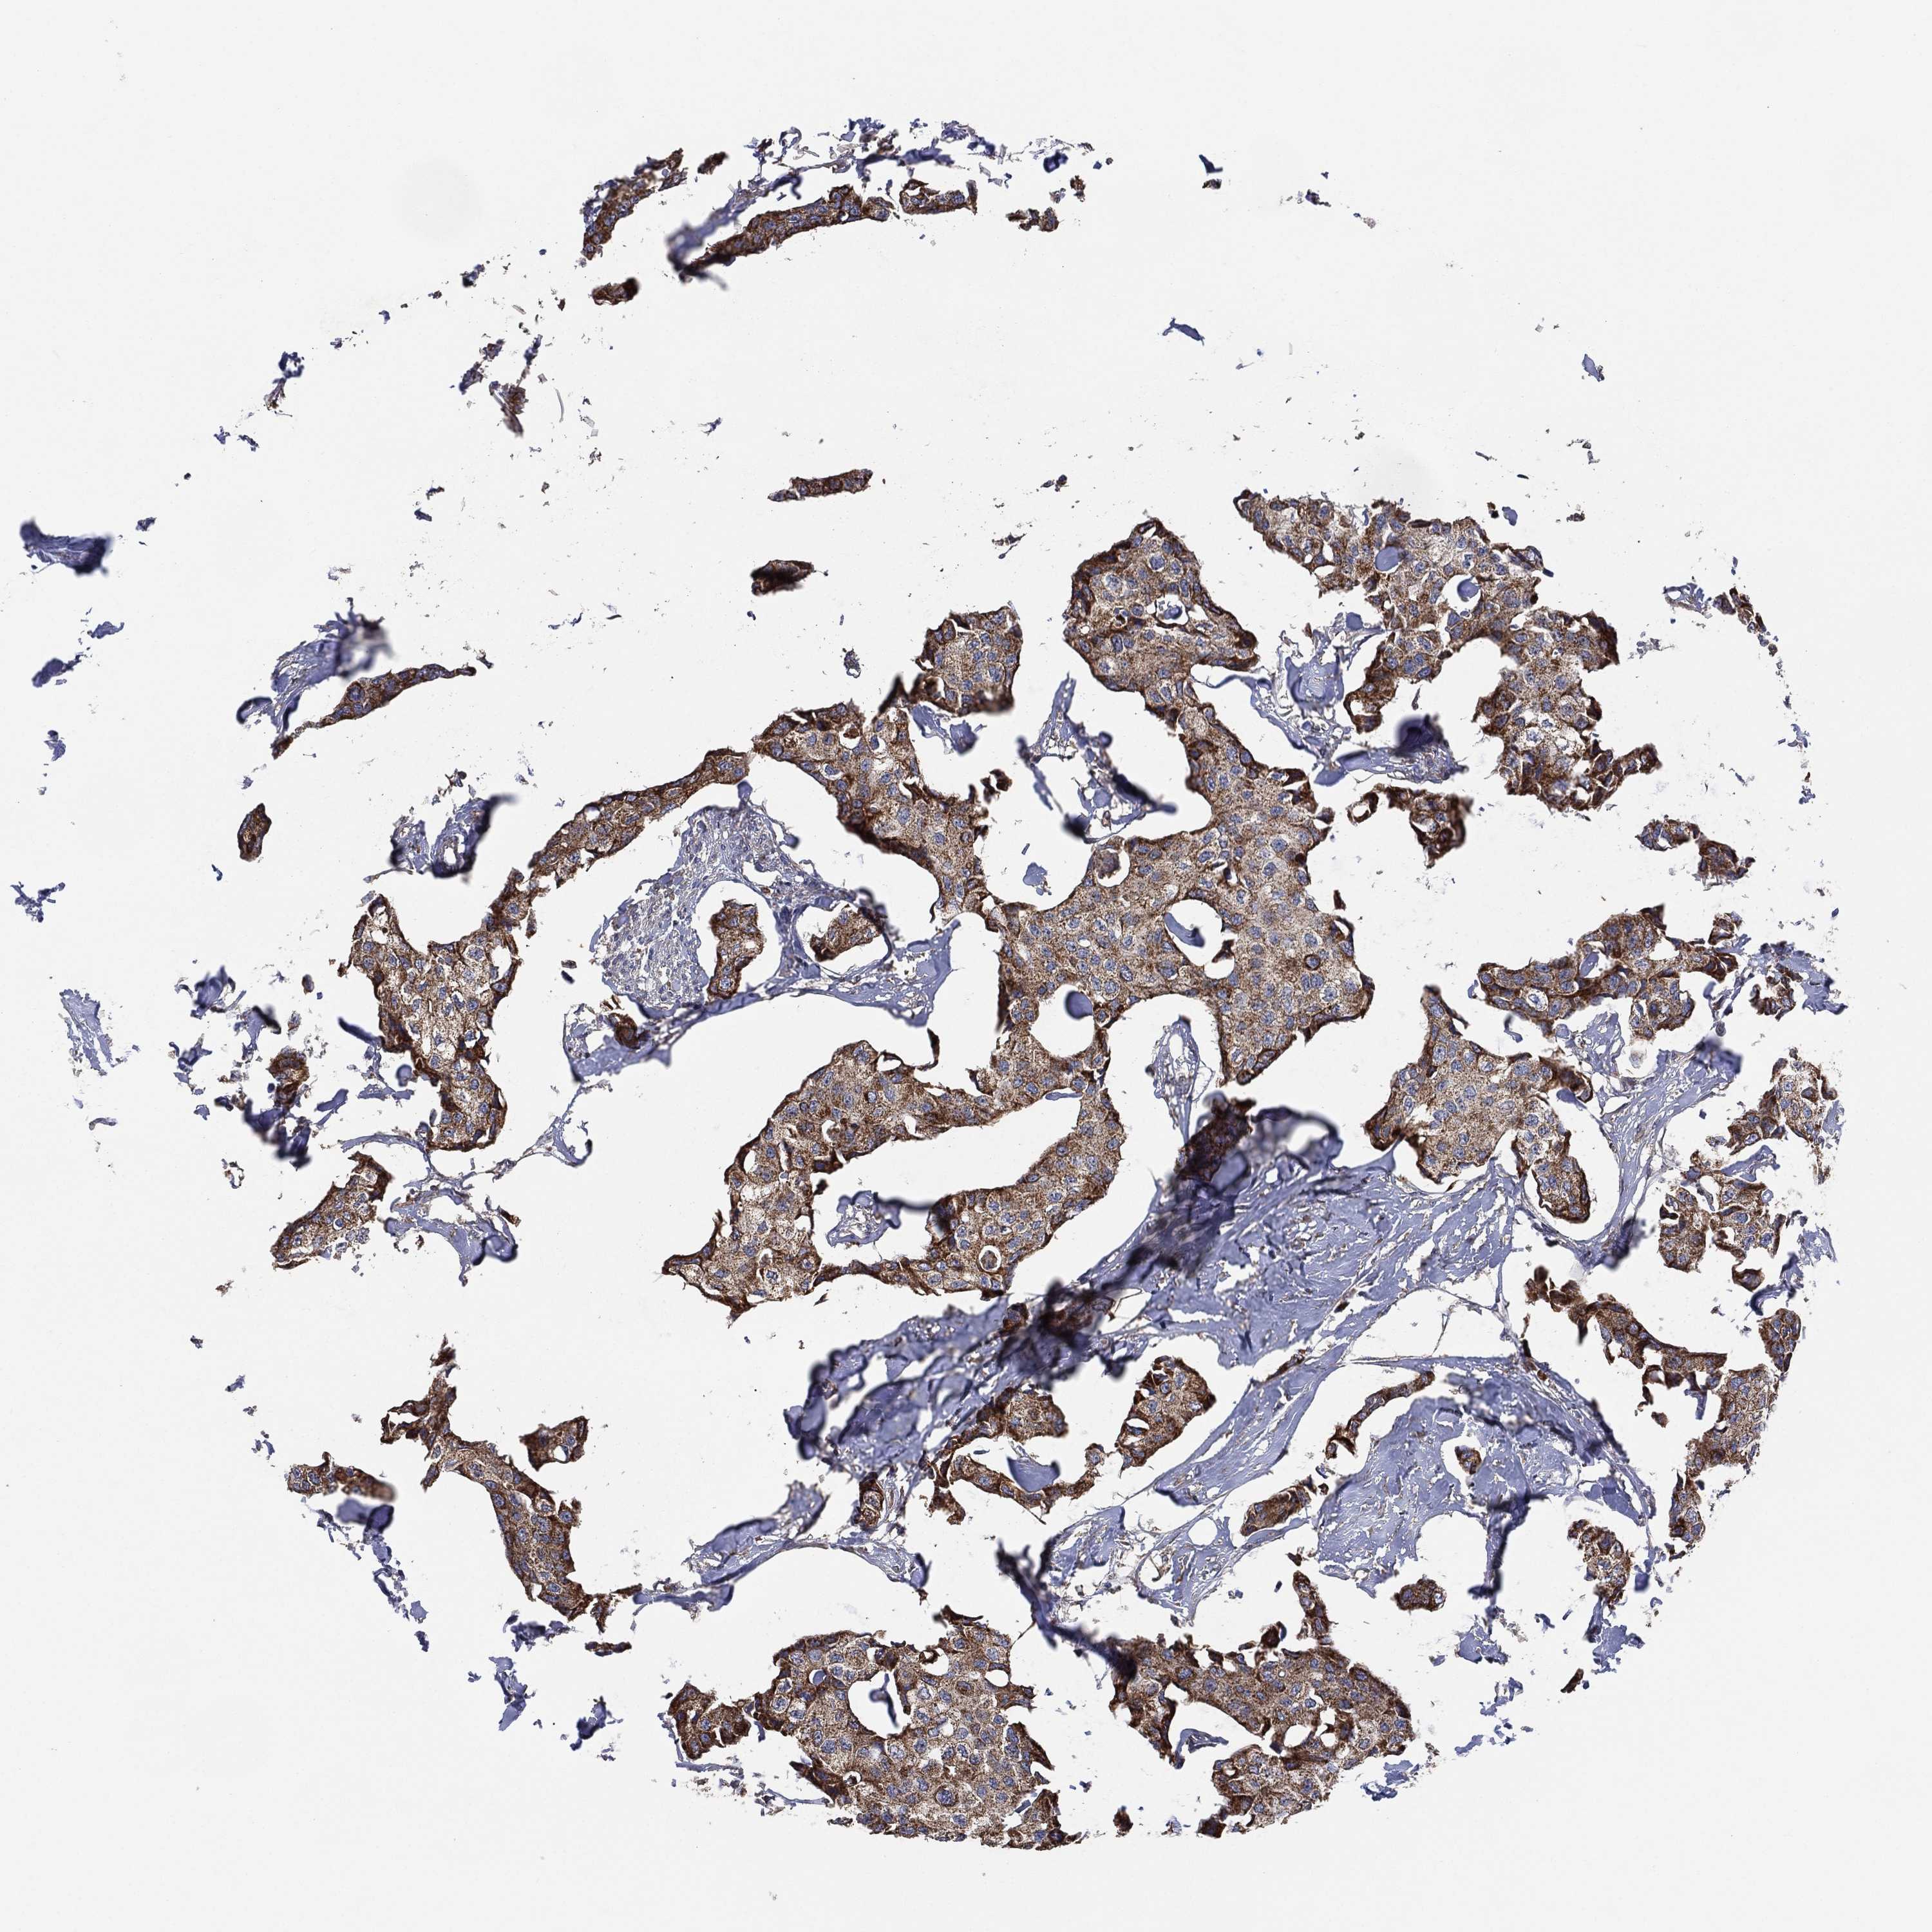

CANCER BREAST CANCER Show tissue menu

BRCA TCGA BRCA VALIDATION PROTEIN EXPRESSION